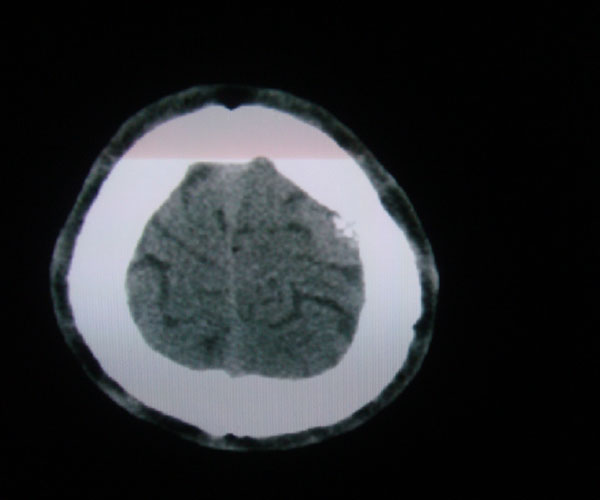

以下是引用zhangzhongshou在2008-6-7 12:49:00的发言:[br]左顶骨嗜酸性肉芽肿可能性大,建议ect及其他检查,除外转移瘤的可能。